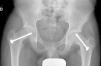

Mooney et al.43 realizaron una encuesta entre los miembros POSNA para valorar el manejo de la ECF. El 57% de los encuestados aconsejaban un tratamiento urgente (menor de 8 h), el 31% un tratamiento preferente y un 12% una reducción electiva. La reducción incidental era el método preferido por el 84% de los encuestados, mientras que el 11,8% preferían la reducción manipulativa formal (completa). El 64,6% desaconsejaba la descompresión capsular como parte del tratamiento de las ECF inestables y la fijación con un tornillo fue utilizada por el 57,4% de los encuestados, mientras que la fijación con 2 tornillos lo fue para el 40,3%. El riesgo de desarrollar una ECF contralateral en un paciente con ECF unilateral es de 2,335 veces mayor que el riesgo de una ECF inicial44, por lo que algunos autores aconsejan la fijación profiláctica contralateral considerando otros parámetros (edad, sexo, estado endocrino, preferencias del enfermo-familia…). A pesar de la evidencia científica de la fijación profiláctica contralateral, la mayoría de cirujanos que respondieron a la encuesta no optaron por este tratamiento43 (figs. 7 y 8).